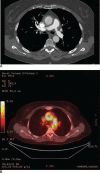

Results: Of the 160 IgG4-RD patients in this cohort, 36 (22.5%) had large-vessel involvement. The mean age at disease onset of the patients with large-vessel IgG4-RD was 54.6 years. Twenty-eight patients (78%) were male and 8 (22%) were female. Thirteen patients (36%) had primary IgG4-related vasculitis and aortitis with aneurysm formation comprised the most common manifestation. This affected 5.6% of the entire IgG4-RD cohort and was observed in the thoracic aorta in 8 patients, the abdominal aorta in 4, and both the thoracic and abdominal aorta in 3. Three of these aneurysms were complicated by aortic dissection or contained perforation. Periaortitis secondary to RPF accounted for 27 of 29 patients (93%) of secondary vascular involvement by IgG4-RD. Only 5 patients demonstrated evidence of both primary and secondary blood vessel involvement. Of those treated with rituximab, a majority responded positively.

Conclusions: IgG4-RD is a distinctive, unique, and treatable cause of large-vessel vasculitis. It can also involve blood vessels secondary to perivascular tumefactive lesions. The most common manifestation of IgG4-related vasculitis is aortitis with aneurysm formation. The most common secondary vascular manifestation is periaortitis with relative sparing of the aortic wall. Both primary vasculitis and secondary vascular involvement respond well to B cell depletion therapy.